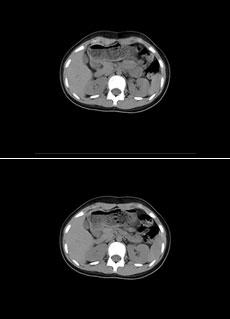

The top image uses a standard dose of 140mA and has not been enhanced. The bottom image uses half the dose (70 mA) and has been post-processed with GOPView CT. The bottom image offers less noise and increased sharpness with 50% of the standard dose.

GOPView CT uses a proprietary and adaptive algorithm, GOP, which enhances CT output images, leading to greater diagnostic confidence. In some implementations, users may use a lower patient dose while maintaining image quality. This type of dose reduction benefits both patents and hospitals. For patients, the low dose translates to less risk without sacrificing image quality or diagnosis accuracy. Hospitals using GOPView CT in this manner will experience decreased wear and tear on X-ray tubes.